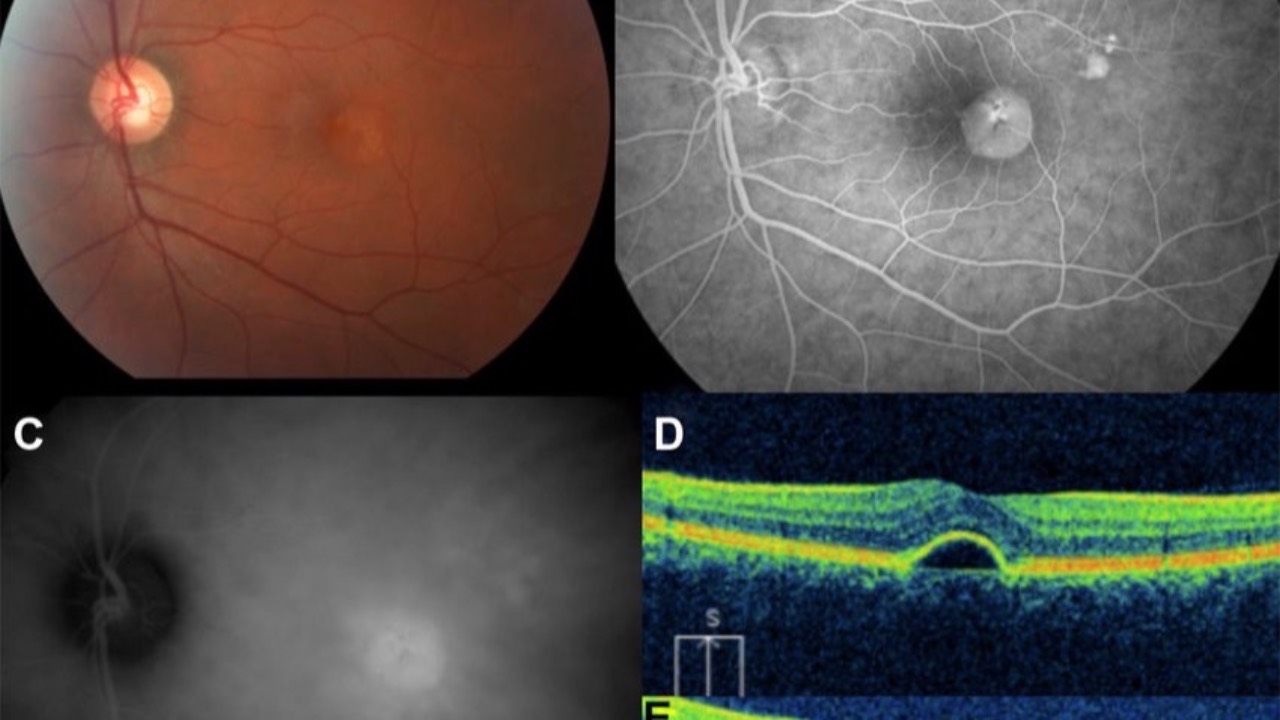

Central Serous Chorioretinopathy Update

Does treatment really even matter?...

Central Serous Chorioretinopathy (CSCR) presents a unique challenge in our practices, characterized by subretinal fluid accumulation beneath the macula. As the fourth most common retinal condition, it requires careful consideration when we approach management...